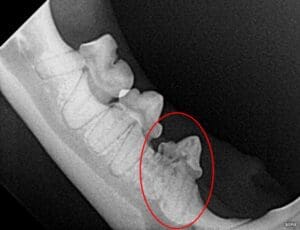

- Tooth resorption is another common oral disease in cats, much more so than in dogs or humans. Tooth resorption is the destruction of the hard tissue of the tooth caused by the body’s own cells. No one knows what triggers this destruction, but it can lead to the loss of many or all the teeth. Some tooth resorption occurs above the gumline and can be seen during an awake exam, but in other cases it may affect just the roots and can only be seen with dental radiographs.

Example of tooth resorption on a cat’s dental x-ray